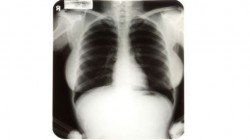

Les poumons de Marylin Monroe

27 juin 2010 : prise en octobre 1954 à l’hôpital Cedars-Senai (une clinique privée de Los Angeles), la radio des poumons de la magnifique actrice attirait toutes les convoitises – puisque laissant deviner sa poitrine. Les trois clichés ont été vendus 45.000 dollars.

(AFP)